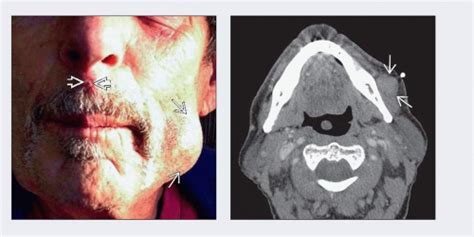

Learn more about the appearance of merkel cell carcinoma by viewing clinical photos of the cancer and how it compares to other skin cancers. Peter, 2011 via wikimedia commons. Merkel cell carcinoma occurs when something goes wrong within these cells and causes them to grow uncontrollably. See pictures of this cancer type and learn about its symptoms. An infrequent but highly malignant type of skin cancer. Merkel cell carcinoma is a rare and a highly aggressive primary skin cancer that grows rapidly and is how is merkel cell carcinoma diagnosed? Merkel cell carcinoma (mcc) is a rare but aggressive neuroendocrine tumour of the skin with high rate of local recurrence and distant metastatic potential leading to poor outcomes. View below our library of basal cell carcinoma pictures. Merkel cell carcinoma (mcc) is a rare and aggressive skin cancer occurring in about 3 people per 1,000,000 members of the population. Merkel cell carcinoma is diagnosed at an average age of 75. Figure 1 primary mcc, chin. Merkel cell carcinoma is a rare type of skin cancer that may initially resemble a harmless mole, but in fact is very aggressive, can spread throughout the body, and is potentially fatal, joshua zeichner, director of cosmetic and clinical research in dermatology at mount sinai in new york city, tells allure. The reported incidence of mcc has more than tripled in the past 20 years1.

Merkel cell carcinoma is different from other skin cancers in that it does not have a common identifiable trait across all cases. Squamous cell carcinoma is more likely to develop on body parts exposed to sunlight. What your skin says about your health slideshow: Figure 1 primary mcc, chin. This means that about 60 percent of people diagnosed with mcc will still be alive after five years. It's possible to find this cancer early because it begins on the skin. The pathogenesis, clinical features, and diagnosis of mcc are discussed here. Merkel cell carcinoma is diagnosed at an average age of 75. Merkel cell carcinoma is a highly aggressive primary cutaneous neuroendocrine carcinoma primarily affecting elderly and immunosuppressed individuals. The reported incidence of mcc has more than tripled in the past 20 years1. Merkel cell carcinoma klaus d. Merkel call carcinoma also affects younger people whose immune system is weakened. An infrequent but highly malignant type of skin cancer.